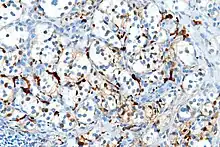

S100 immunostain highlighting the sustentacular cells in a paraganglioma

With immunohistochemistry, the chief cells located in the cell balls are positive for chromogranin, synaptophysin, neuron specific enolase, serotonin, neurofilament and Neural cell adhesion molecule; they are S-100 protein negative. The sustentacular cells are S-100 positive and focally positive for glial fibrillary acidic protein. By histochemistry, the paraganglioma cells are argyrophilic, periodic acid Schiff negative, mucicarmine negative, and argentaffin negative.